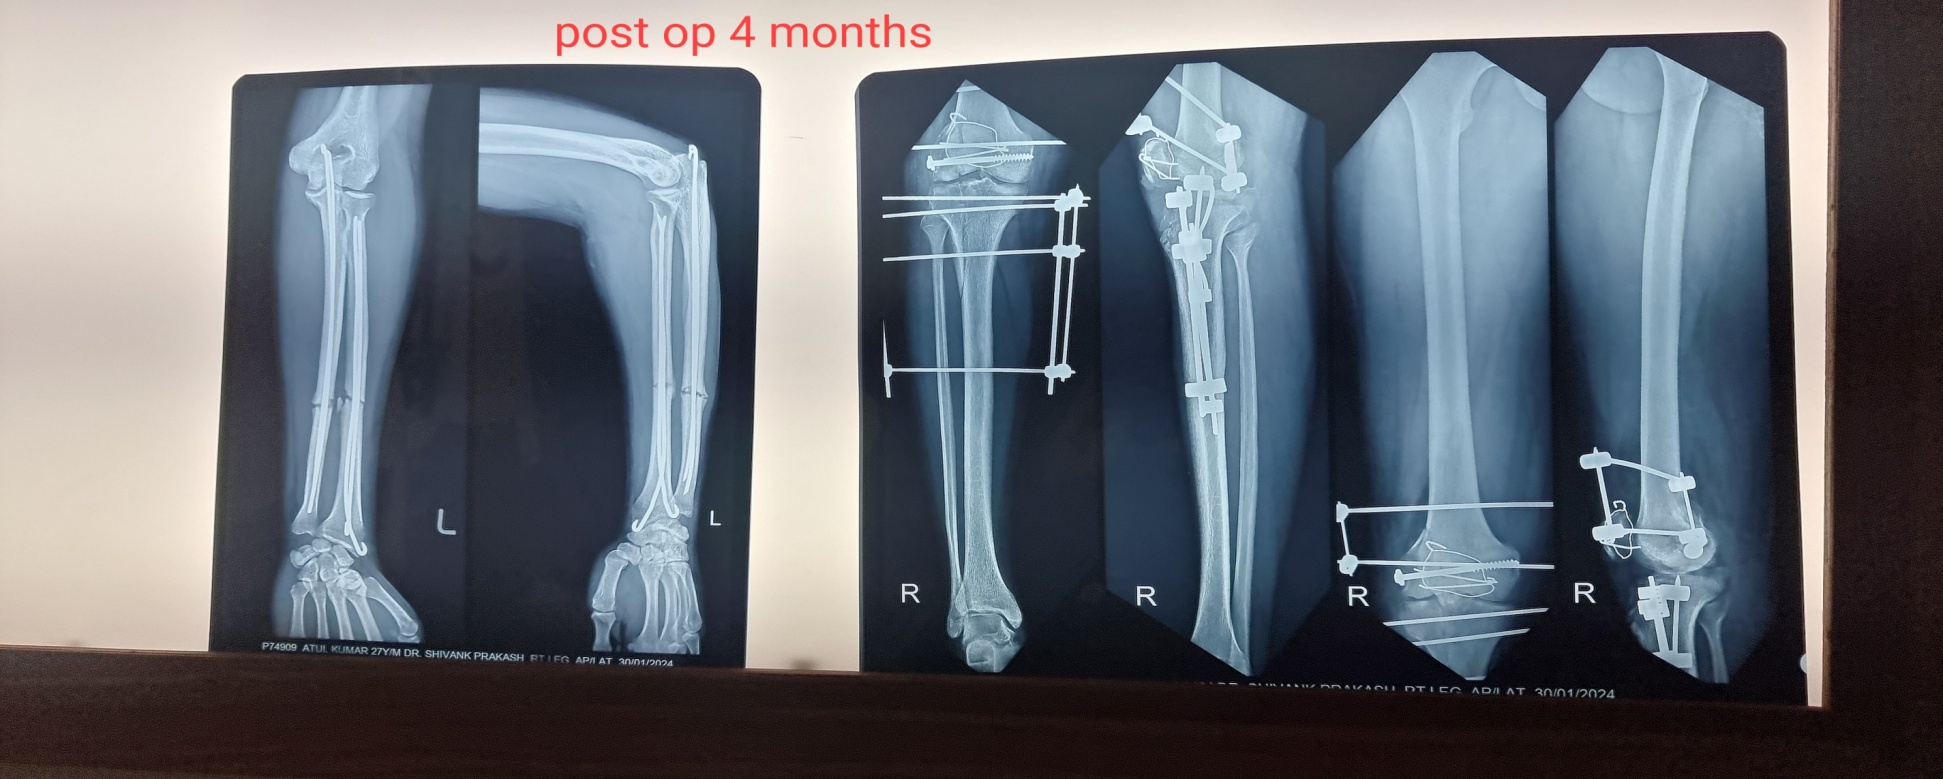

A 26 y-old male sustained a Type IIc Fraser and Type IVb Agarwal and Singh Floating knee injury on the right side. This included displaced intra-articular fractures of the lateral femoral condyle and lateral tibial plateau, a displaced patellar fracture with Grade II ACL tear and PCL sprain, complex tear of the lateral meniscus, and extensor mechanism rupture. Treatment involved external fixation for ipsilateral shaft fractures of the femur and tibia, along with a physiotherapy rehabilitation protocol for associated soft tissue injuries and tension band wiring for the patellar fracture. The patient achieved a good functional outcome after 2 y of follow-up, as depicted in [fig. 1a-d].

Fig. 1b: Postoperative X-ray at 6 mo follow-up